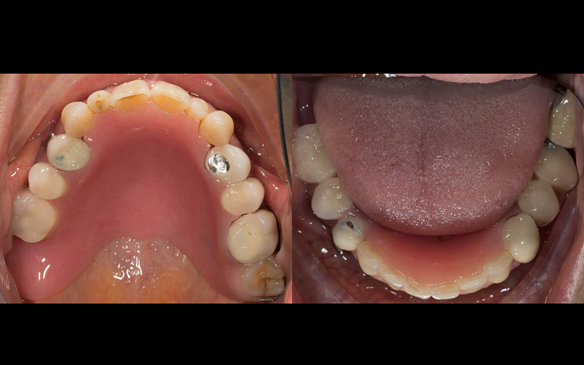

This newsletter describes in step by step detail Angela's transition through immediate partial dentures to crown supported definitive metal based dentures.

This 58 year old woman was referred to me by her general dental practitoner for treatment.

- Generalised Periodontitis; Stage 4, Grade C, Currently Unstable. Risk Factors: Type 1 diabetes. 16, 17 - hopeless prognosis. 14, 24, 26, 27, 34, 37, 44 - guarded prognosis

- Poor marginal fit and poor appearance of crowns and bridgework

The clinical situation and treatment process is shown in detail below with photographs. I (Finlay Sutton) provided the clinical work and Rowan Garstang provided the technical work.